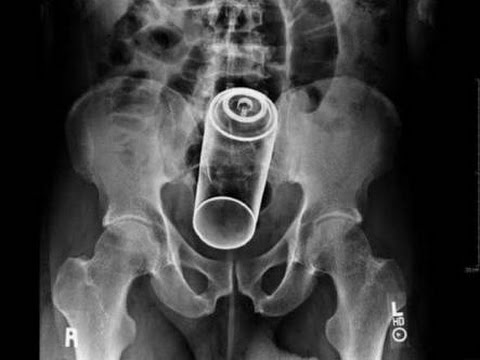

Röntgen filmlerinden "akıl almaz şeyler

Hastane koridorlarına düşenler bilir… Doktora görün, tahlilleri yaptır, röntgenleri çektir falan filan derken sayılmadan ömür gider. Gelin ki bu sefer ilginç şeyler çıkmış ki görün ağzımız açık kaldı…